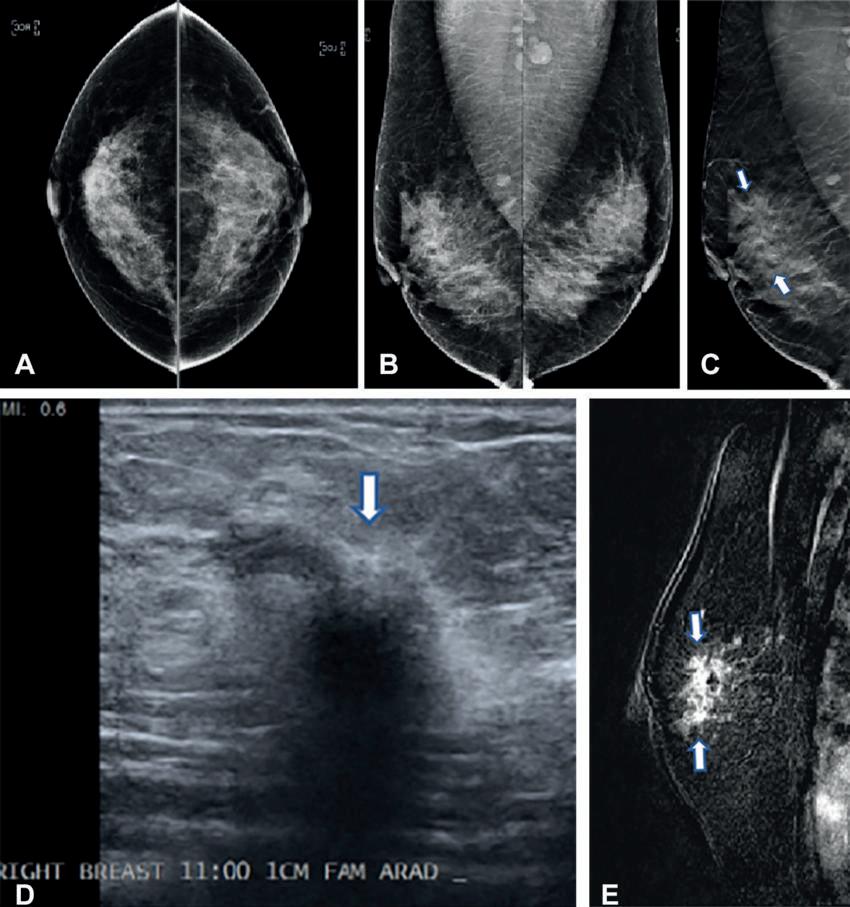

grafía digital craneocaudal bidimensional y (B) Mamografía digital mediolateral bidimensional que muestran tejido mamario heterogéneamente denso sin anomalías. (C) Imagen de tomosíntesis mamaria digital mediolateral que muestra una sutil distorsión arquitectónica (flechas) que se extiende superiormente desde el nivel del pezón. (D) La imagen ecográfica diana de la mama derecha muestra una masa irregular, hipoecoica y muy sospechosa (flecha). La biopsia central guiada por ecografía arrojó carcinoma ductal invasivo con carcinoma ductal extenso in situ (T2N0M0; receptor de estrógeno positivo, receptor de progesterona positivo y receptor del factor de crecimiento epidérmico humano 2 negativo). (MI) La resonancia magnética de la mama derecha adquirida para evaluar la extensión de la enfermedad muestra un artefacto de clip en la cara superior de la masa con realce irregular (flechas). No se observaron otras lesiones sospechosas.

Figura 1. Creación de la cohorte de estudio. El diagrama de flujo describe cada criterio de inclusión y exclusión que debe cumplirse para su inclusión en el análisis. Las mujeres con edades entre 40 y 79 años en el momento de la selección y sin antecedentes de cáncer de mama en la mamografía Figura 2. Imágenes en una mujer de 42 años que acude rutina. (A) Mamo- Dra. Emily F. Conant Por Ezequiel Domb Nota de Prensa de la RSNA

una asimetría (flecha). (B) Imagen de tomosíntesis mamaria digital craneocaudal izquierda que no muestra lesión sospechosa sino más bien una superposición de estructuras fibroglandulares y ligamentosas normales.

La detección con mamografía digital bidimensional (2D) sola sigue siendo el estándar de atención en muchos sitios, pero tiene sus limitaciones debido a su incapacidad para detectar algunos tipos de cáncer. Cada vez hay más evidencia de que el DBT, una tecnología más avanzada, tiene una tasa de detección de cáncer de mama más alta debido a su capacidad para capturar múltiples imágenes de rayos X de la mama desde diferentes ángulos en lugar de la típica imagen única obtenida con un 2D estándar. La mamografía DBT es especialmente beneficioso para las mujeres con tejido mamario más denso.